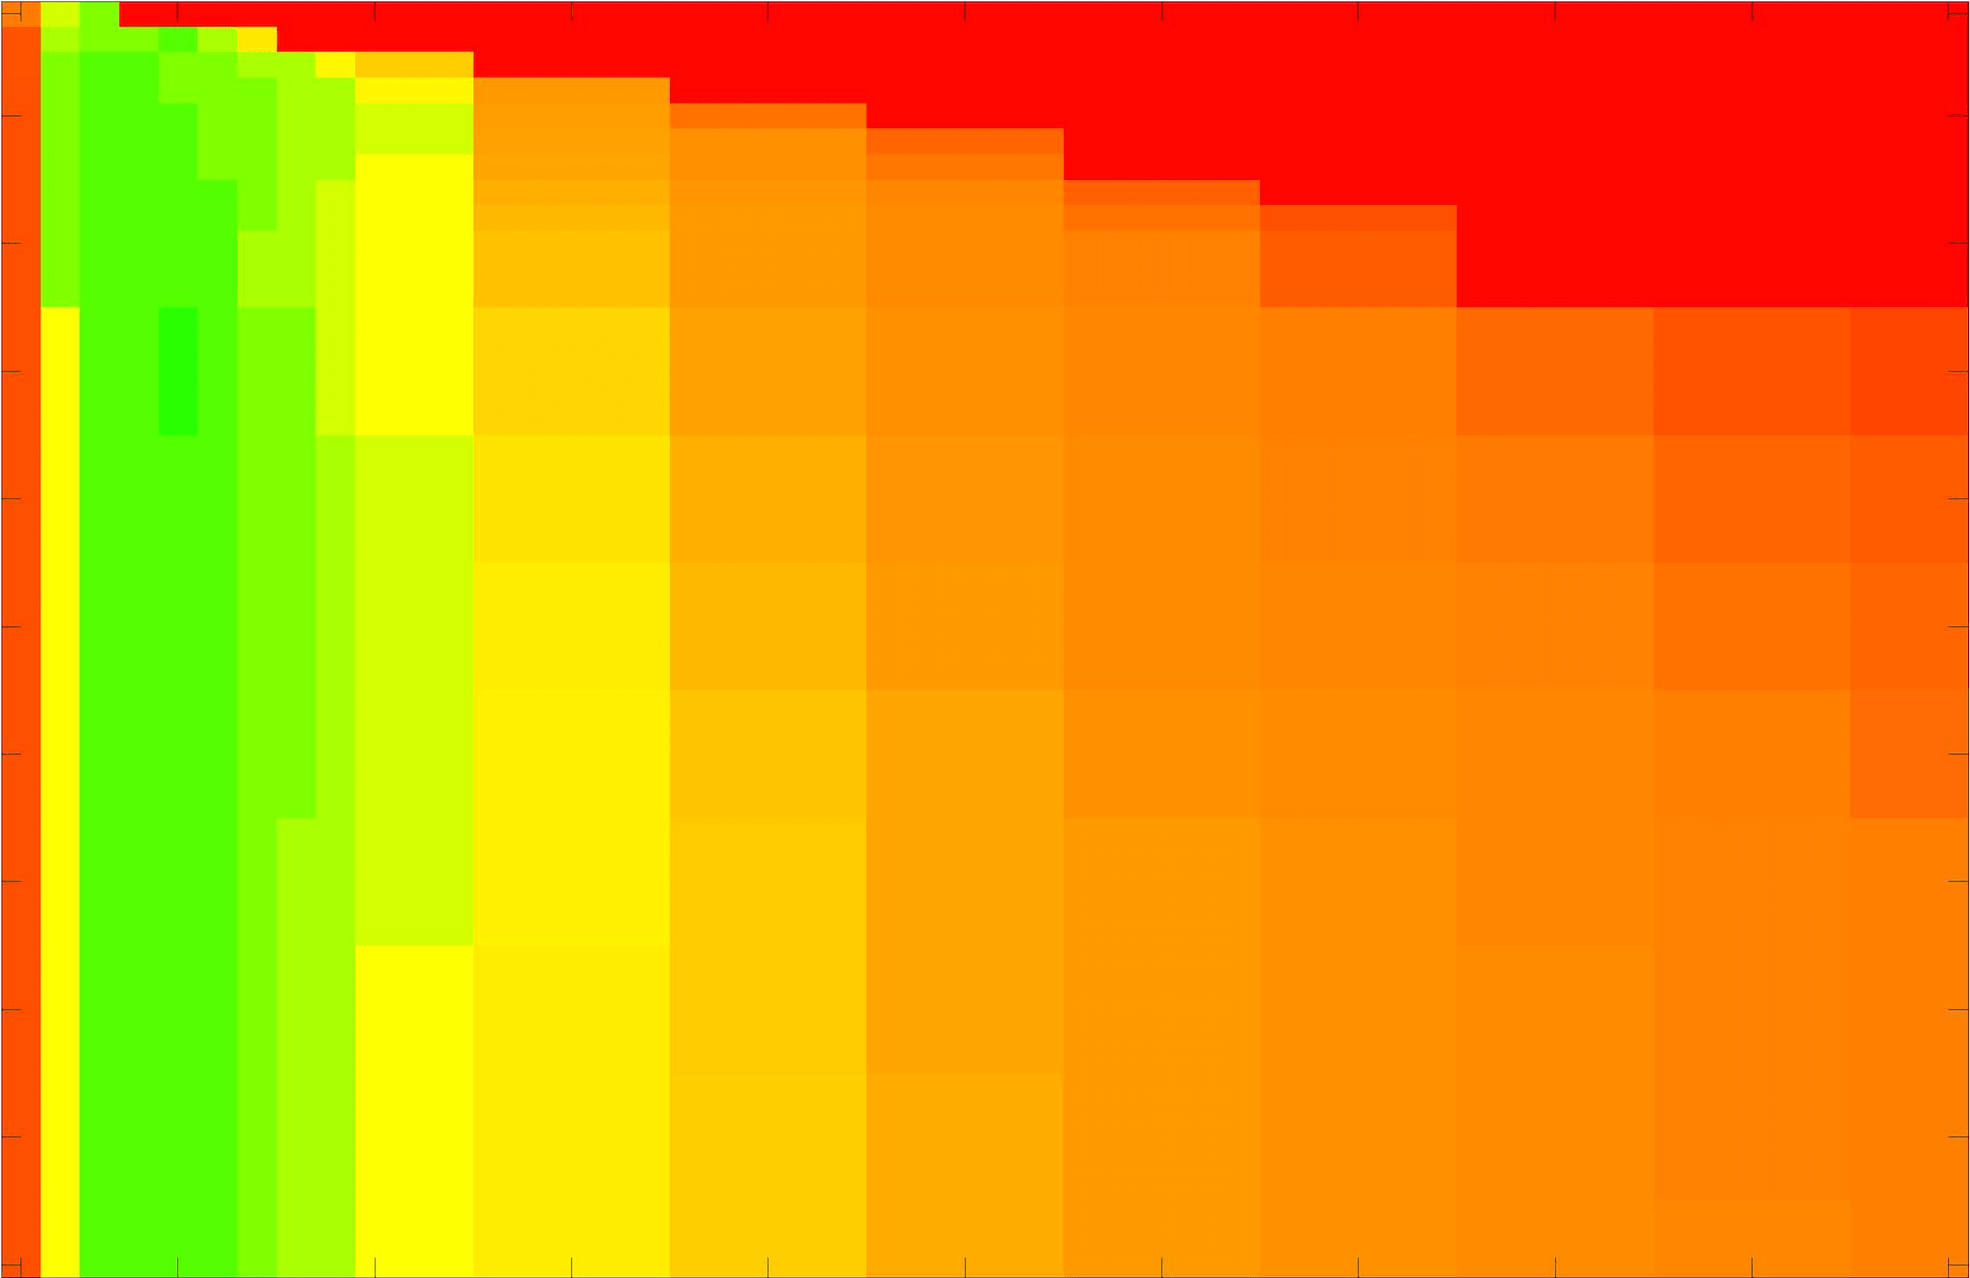

where refers to the number of points in the enclosed region. This takes values in the range , with higher TC values indicating a more accurate segmentation. In the following we will represent accuracy visually from red () to green (), with the intermediate scaling of colours used shown in Fig. 8. This will be particularly relevant in §7.2.

The TC values for the parameter sets are presented as heatmaps in Figs. 11–13. A heatmap is a convenient way to display accuracy results for hundreds of tests concisely. In Fig. 9 we give an example heatmap with the same axes used for those in Figs. 11–13. For each of the combinations of parameter values we give the TC value of the segmentation result and represent it by the appropriate colour. The corresponding colour scale is shown in Fig. 8. Qualitatively, the more green areas of the heatmap the more accurate the model is for a wider set of parameters. Example results for Test Image 5 when varying (with ) for the proposed model are given in Fig. 10. Here it can be seen what each accuracy result corresponds to visually.

Note. The axes have been removed from the heatmaps in Figs. 11–13 for presentational clarity. However, to be explicit, the axes used in all heatmaps are the same as those in Fig. 9.

Synthetic Images. These results are presented in Fig. 11. For Test Images 1–2 we see poor parameter robustness from all competing models, except for GAV which performs reasonably well. However, the proposed model has minimal parameter sensitivity for these images, with good results achieved for almost every combination of values tested. For Test Image 3 all models have a reasonable parameter range (except for RSF), however the proposed model gives better quality results for a wider parameter range. The other models achieve reasonable results here as the foreground intensity of the ground truth is greater than the background , whereas for Test Images 1–2 they are equal . These results highlight the key advantage of the proposed model.

Real Images. In Fig 12 we present results for Test Images 4–6. Here, the proposed model performs in a similar way to its competitors because these images are more typical selective segmentation problems in the sense that there is a clear distinction between the foreground and background intensities. In particular, the values in each case are: Test Image 4 , Test Image 5 , and Test Image 6 . It can be seen that the proposed model is competitive compared to previous approaches. The performance is quite poor for Test Image 5, but is arguably still the best for this challenging case. In Fig. 13 we present results for Test Images 7–9. Here the proposed model outperforms previous approaches significantly for each image. This is mainly due to the type of image considered. Specifically, the true intensities are: Test Image 7 , Test Image 8 , and Test Image 9 . The proposed model is capable of achieving results where , with other models failing completely in these cases.